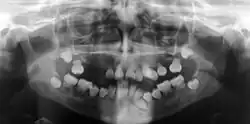

| Preoperative panoramic radiographs showing features of dentin dysplasia type I | |

Dentin dysplasia (DD) is a rare genetic developmental disorder affecting dentine production of the teeth, commonly exhibiting an autosomal dominant inheritance that causes malformation of the root. It affects both primary and permanent dentitions in approximately 1 in every 100,000 patients.[1] It is characterized by the presence of normal enamel but atypical dentin with abnormal pulpal morphology. Witkop[1] in 1972 classified DD into two types which are Type I (DD-1) is the radicular type, and type II (DD-2) is the coronal type. DD-1 has been further divided into 4 different subtypes (DD-1a,1b,1c,1d) based on the radiographic features.[2]

In other words, affected primary teeth usually have abnormal -shaped or shorter than normal roots. “Crescent/half-moon shaped” pulp chamber remnant in permanent teeth can be seen on x-rays. The roots may appear to be darker or radiolucent/pointy and short with apical constriction. Dentine is laid down abnormally and causes excessive growth within the pulp chamber. This will reduce the pulp space and eventually cause incomplete and total pulp chamber obliteration in permanent teeth.[12][13] Sometimes periapical pathology or cysts can be seen around the root apex.[11] Most cases of DD associated with peri-apical radiolucency/ pathology have been diagnosed as radicular cysts, but some of them have been as diagnosed peri-apical granuloma instead.[14]